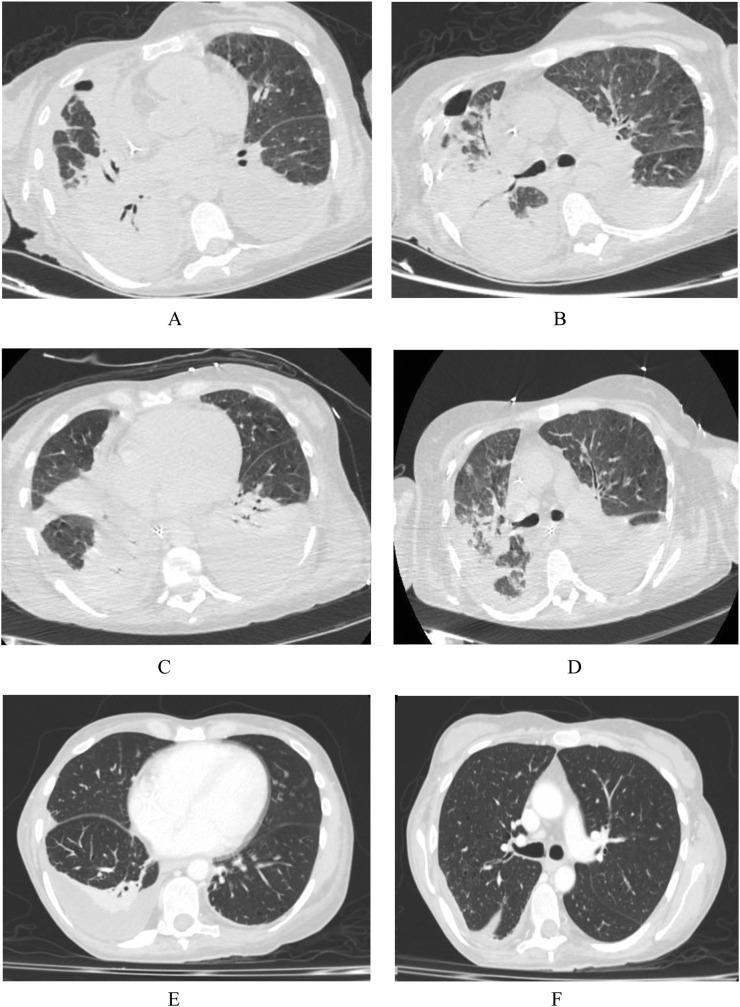

We analyzed the case of a 49-year-old woman with HIV infection off-therapy with poor viro-immunological compensation, not vaccinated for SARS-COV-2, hospitalized for lobar pneumonia and severe COVID19-related respiratory failure in intensive care unit (ICU). The hospitalization was complicated by bacteraemic ventilator-associated pneumonia (VAP) caused by multidrug-resistant (MDR-AB) isolated on pleural fluid culture, treated with colistin and cefiderocol for about 3 weeks. The molecular research of MDR-AB on transtracheal aspirate was negative following this therapy. The aim is to show the safety, efficacy and tolerability of colistin-based combination therapy with cefiderocol for infection in HIV-infected patient.

我们分析了一例49岁的HIV感染女性病例,该患者停止治疗后病毒免疫补偿不佳,未接种SARS-CoV-2疫苗,因大叶性肺炎和严重的COVID-19相关呼吸衰竭入住重症监护病房(ICU)。住院期间并发了由胸腔积液培养分离出的多重耐药鲍曼不动杆菌(MDR-AB)引起的菌血症性呼吸机相关性肺炎(VAP),用黏菌素和头孢地尔治疗约3周。治疗后经气管抽吸物对MDR-AB的分子研究结果为阴性。目的是展示黏菌素联合头孢地尔治疗HIV感染患者感染的安全性、有效性和耐受性。